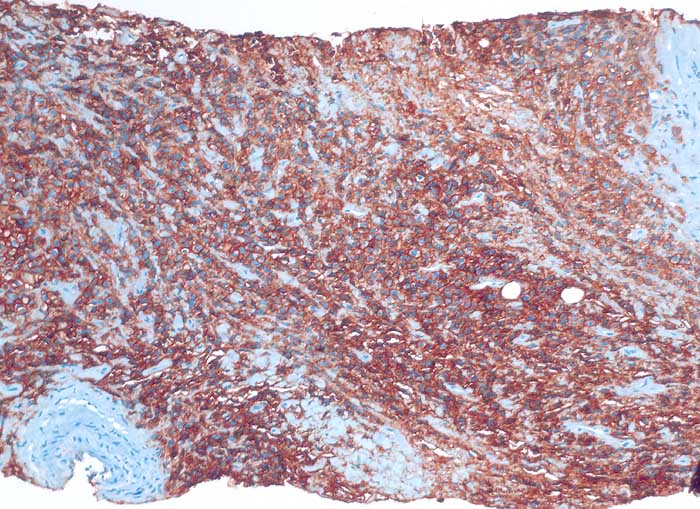

pit/ Diffuses grosszelliges B-Zell Lymphom

Diffuses grosszelliges B-Zell Lymphom

Diffuse grosszellige B-Zell Lymphome treten nicht selten in extranodalen Lokalisationen auf und können klinisch als Karzinom fehlgedeutet werden. Bei ungewöhnlicher Zytomorphologie eines malignen Tumors sollte deshalb immer auch an die Möglichkeit eines nicht epithelialen Tumors gedacht und der Befund mittels Immunzytochemie weiter abgeklärt werden. Zur Unterscheidung eines Lymphoms von einem epithelialen Tumor eignen sich der panleukozytäre Marker CD45 (LCA) und ein Panzytokeratinmarker oder BerEP4.

Beim ersten Fall handelt es sich um ein primär extranodales Lymphom des Nierenbeckens, das im Urin diagnostiziert wurde. Beim zweiten Fall handelt es sich um ein primär extranodales Lymphom im Bereich der Nebenniere mit Nachweis von Lymphomzellen im Aszites.